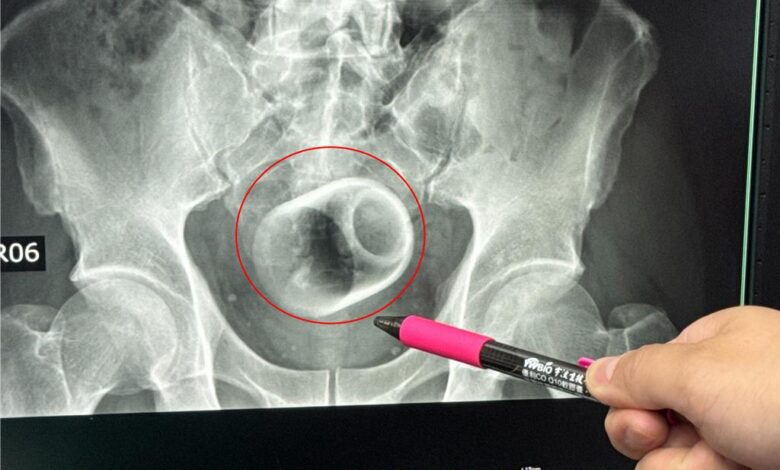

該名患者到院時稱,已經3天無法大便很困擾,害羞不敢提及自己肛門塞了一個杯子,經過X光攝影,可見骨盆腔內有一個直徑約6公分、高約8公分的杯子,杯口朝下,自己當時見狀嚇一大跳,立即安排進手術室,要把杯子拿出來。

醫師起初使用器械要把杯子夾出來,但因杯子光滑無法施力,加上杯身全被大腸包住,部分腸子缺血也造成壞死,後來再使用腹腔鏡,依舊無法順利取出,也擔心把杯子夾碎,傷及患者或造成感染風險,最後只好在肚子上動刀畫開腸子,手術總共歷經2個多小時,最終才取出杯子,同時做好一個人工造口,讓患者能夠暫時解便。